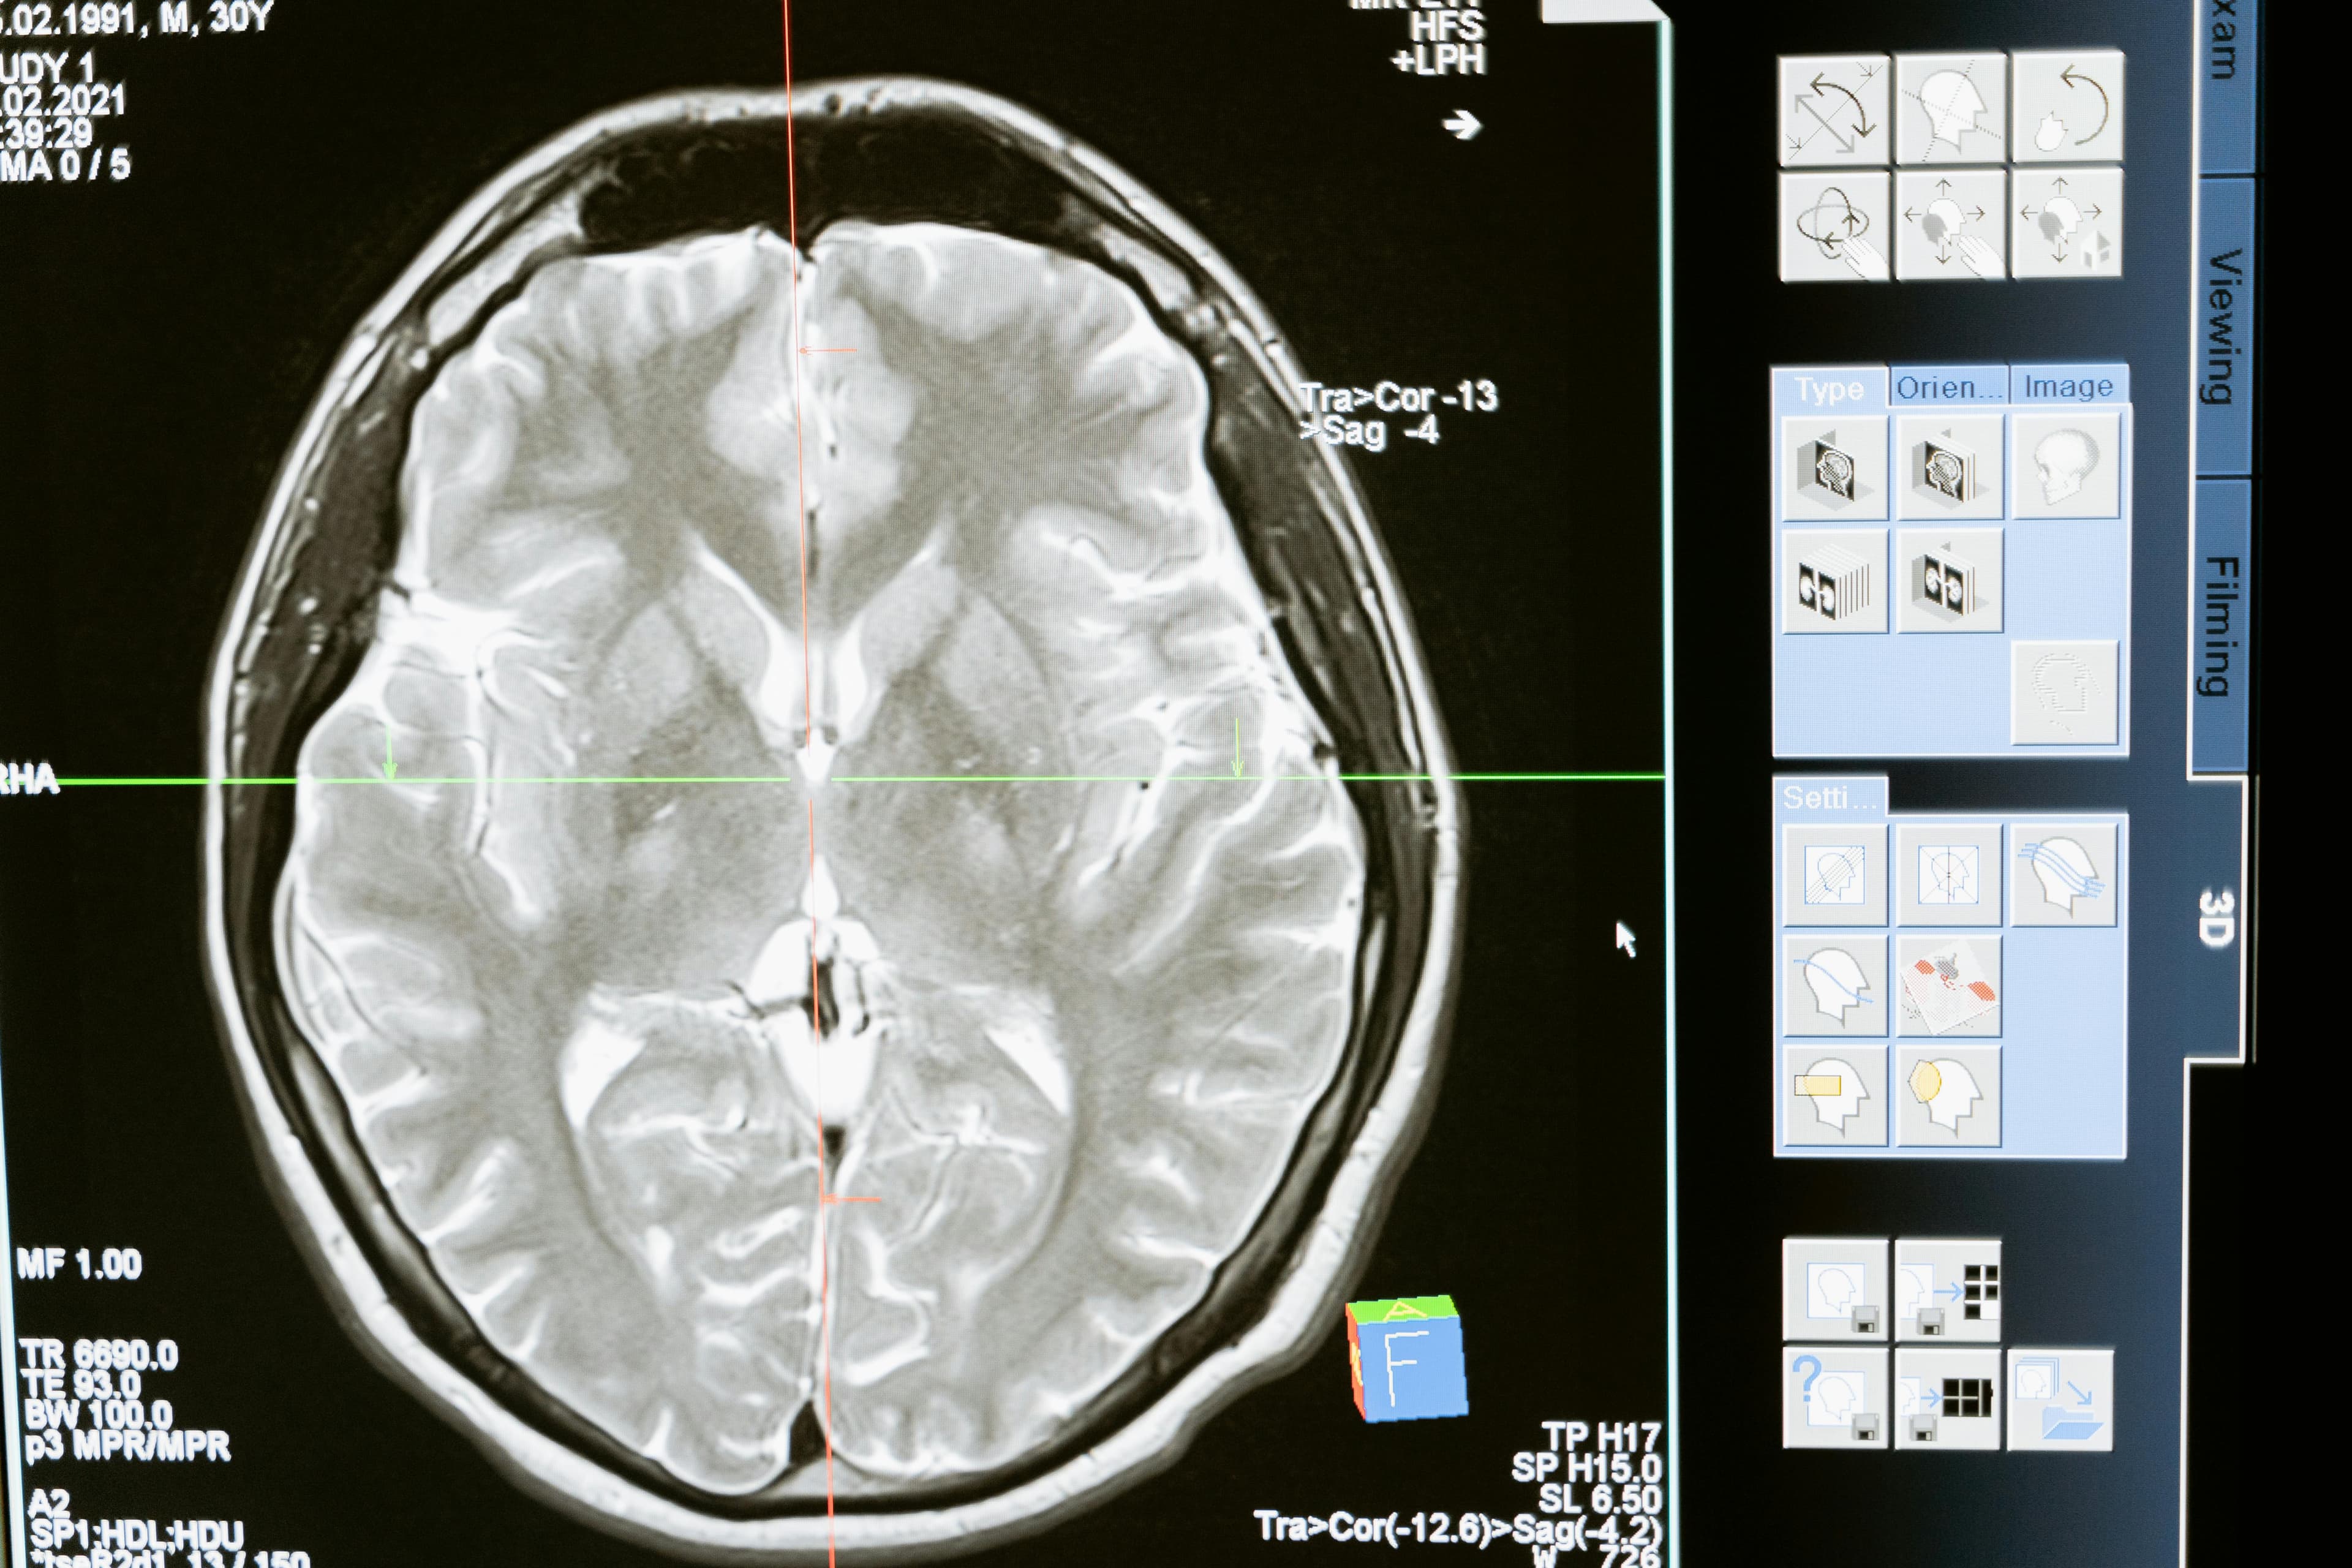

Vitamin D receptors are widely distributed throughout the brain, particularly in areas responsible for memory.

According to experts, Vitamin D acts more like a hormone, influencing various neurological processes. It helps regulate the immune system, reduces inflammation, and supports the clearance of amyloid plaques: protein buildups that are a hallmark of Alzheimer's disease.

Recent studies, including those summarized by Harvard Health and Medical News Today, show that individuals with low levels of vitamin D are significantly more likely to develop dementia. One study found that severe deficiency in vitamin D was associated with a more than twofold increased risk of developing dementia, including Alzheimer’s disease.